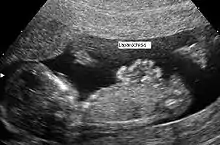

Gastrosquise (do greco-latim squise, fenda) também conhecida como laparosquise ou abdominosquise é uma má-formação congênita caracterizada por defeito na formação da parede abdominal, permitindo que as vísceras abdominais, como estômago e intestinos, saiam por uma abertura. Quase sempre ocorre à direita da região umbilical.[1]

Diferente da onfalocele, onde há envolvimento do cordão umbilical e os órgãos permanecem protegidos, recobertos por peritônio; na gastrosquise, as vísceras abdominais ficam soltas, não há membrana cobrindo os órgãos herniados, ficando portanto diretamente expostos ao líquido amniótico.